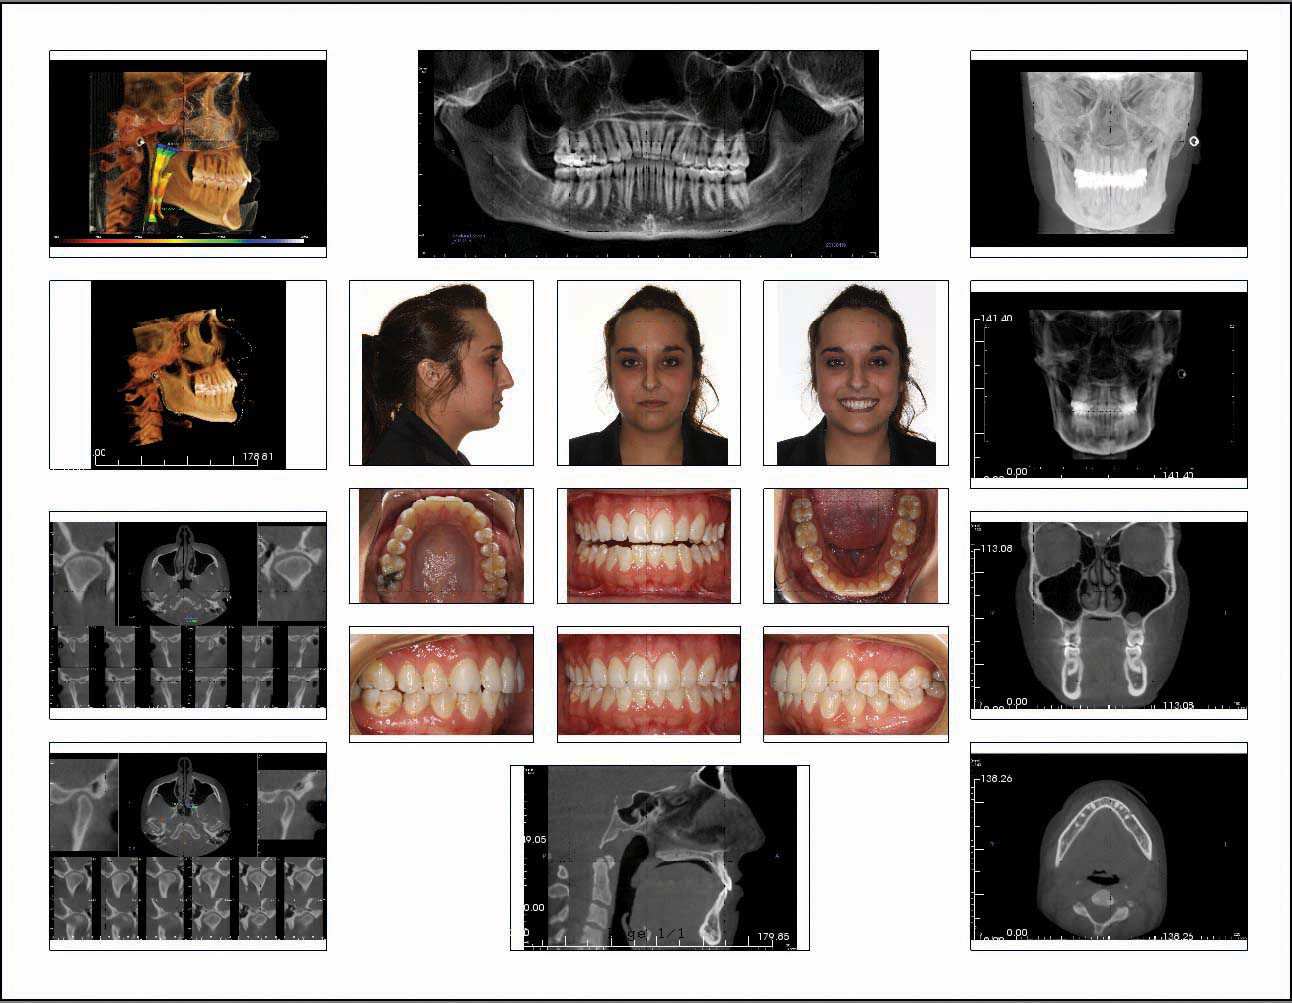

3) Go to the upper right corner of the software and select the "Report" tab. A black template outline will appear. We have provided Imaging Sciences a copy of our default report settings to provide to all users at no cost. You should not have to replicate its creation. Contact Imaging Sciences International support (215- 997-5666) to obtain our default settings to create the boxes shown for populating with images. We do not have the ability to provide a link or the report in any form. Alternatively, you may customize your preference for an image layout and save it as your default report setting.

4) You will then populate the loaded German Template by building the images listed.

5) The photographic images in the center of the template will be imported from a file on your computer or a camera memory card. Double-click on the box to bring up the "Single Image Box Properties" window, then browse to your photo storage location and select the correct image. Click "OK."

6) The tabs along the top of the screen will be used to build the images for the rest of the German Template.

7) Image creation is described in the following steps. After each image is created, zoom in by pressing the CTRL key and then clicking on the image and dragging the mouse up/down to fit the image to the screen.

8) The German template is complete! Click on the report tab to view the populated template.

If any images are missing, ensure that the spelling and case of the image title are identical to the template label, then resave the missing image(s) to "Capture to Gallery" to automatically populate the template.